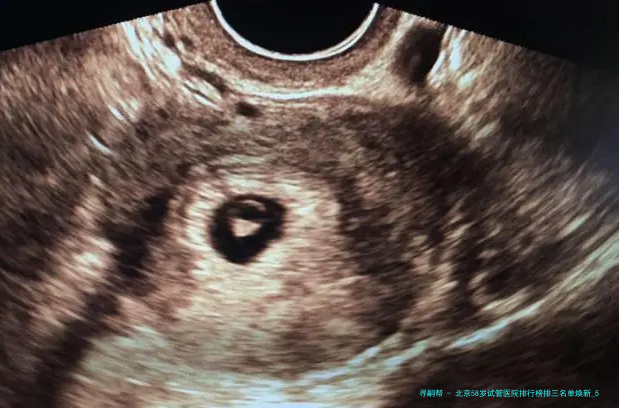

“医生,我58岁AMH值几乎为零,仍旧有可能用自己的卵子做试管吗?”在北京某生殖中心咨询室,一位鬓脚花白的女士紧握化验单的手悄悄发抖——这便是很多超高龄家庭求子路的真实缩影💔。58岁生育堪称“逆天改命”🧬:卵巢功效彻底衰竭、胚胎染色体不同寻常率超80、妊娠并发症风险迅猛上涨……选错医院不仅人财两空,更可能错失后的生育机会!2025年北京具备试管资质的医院达18家,但真实擅长超高龄方案的仅寥寥数家。本文结合新临床数据,揭晓严选前三医院排行、反转策略与性价比方案,让每一分盼望都用在刀刃上!

58岁试管成功的重要在于医院是否拥有个别化促排方案、胚胎基因学筛查(PGT)技术、多科目并发症处理能力。根据2025年北京市辅助生殖质量报告,下面列举三家医院在超高龄领域表现突出(按技术储备、临床数据、患者口碑综合排序):